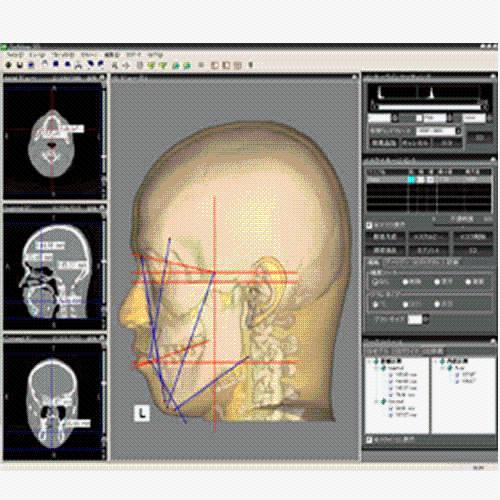

ANYTHINK 经导管主动脉瓣膜置换术分析系统